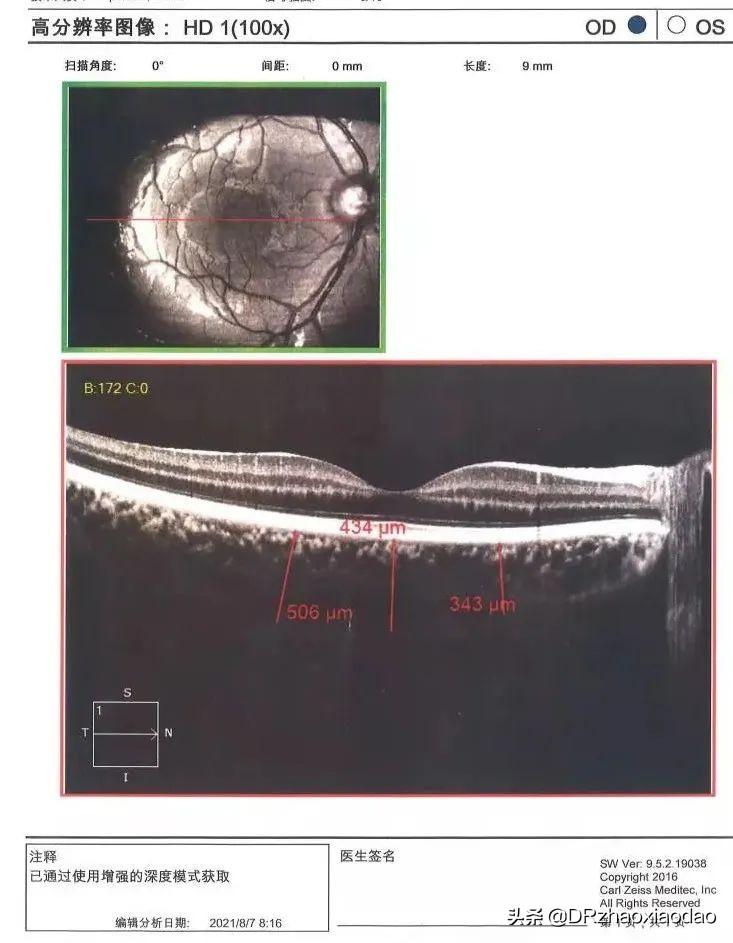

OCT